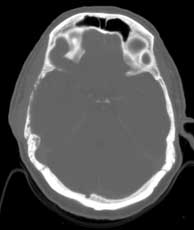

Axial CT bone windows

Findings:

Extensive, permeative destruction involving the squamous portion of the right temporal bone (a). Post-op bilateral mastoidectomies (b).